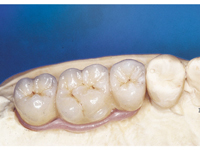

Protetické řešení může být pomocí můstku, který je kotvený na implantátech nebo pomocí jednotlivých korunek na implantátech.

V zásadě je možné do těchto můstků zařadit i přirozené zuby, zejména pokud je potřeba tyto zuby ošetřit proteticky

- korunkami. Korunky nebo můstky mohou být na implantáty nacementovány nebo přišroubovány.